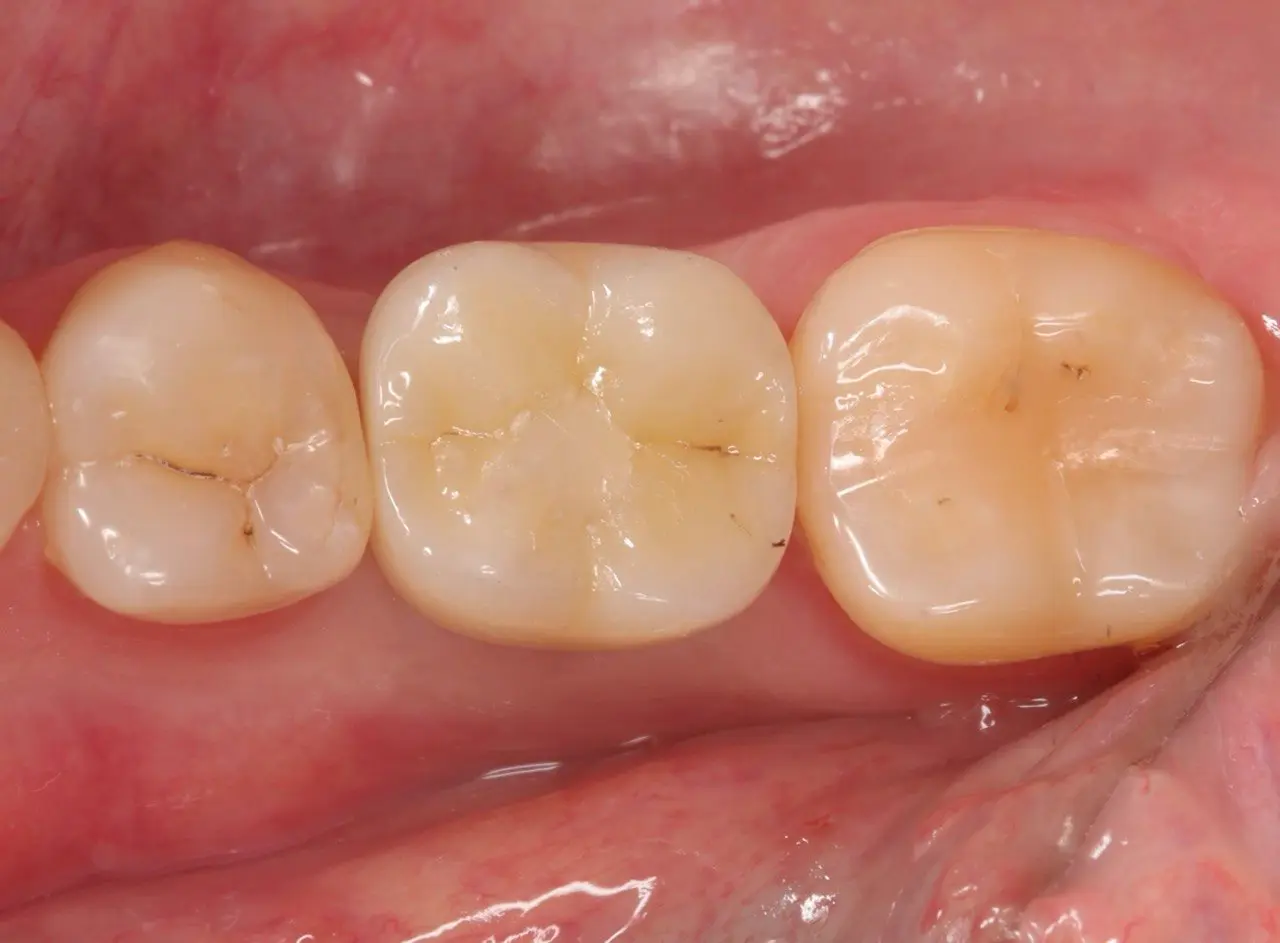

Імплантація з відновленням анатомії зуба

Для відновлення функції втраченого зуба проведено імплантацію з подальшим формуванням ясен під майбутню коронку.

Завдяки цифровому оптичному відбитку виготовлено коронку, що точно відтворює анатомію природного зуба.

Фінальний етап — фіксація та делікатна корекція прикусу.

Результат: стабільність, естетика та повноцінна функція жування.